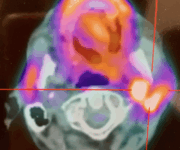

2. Scintigrafia tiroidea

La scintigrafia con Tc-99m o I-123 consente di visualizzare la distribuzione del tessuto tiroideo funzionante e identificare eventuali aree iperfunzionanti (noduli autonomi) o assenza di captazione.

Questa informazione è essenziale per distinguere tra Morbo di Basedow (captazione diffusa) e gozzo multinodulare tossico (captazione disomogenea), oltre che per escludere sospetti di neoplasia, in cui la captazione può essere assente.